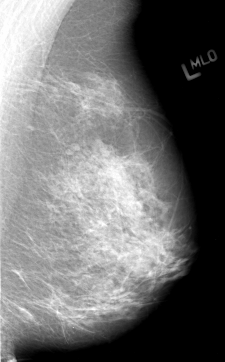

ics_version 1.0 filename B-3012-1 DATE_OF_STUDY 23 5 1995 PATIENT_AGE 53 FILM FILM_TYPE REGULAR DENSITY 3 DATE_DIGITIZED 24 4 1997 DIGITIZER LUMISYS LASER SEQUENCE LEFT_CC LINES 4256 PIXELS_PER_LINE 2752 BITS_PER_PIXEL 12 RESOLUTION 50 NON_OVERLAY LEFT_MLO LINES 4336 PIXELS_PER_LINE 2696 BITS_PER_PIXEL 12 RESOLUTION 50 NON_OVERLAY RIGHT_CC LINES 4136 PIXELS_PER_LINE 3152 BITS_PER_PIXEL 12 RESOLUTION 50 OVERLAY RIGHT_MLO LINES 4216 PIXELS_PER_LINE 3192 BITS_PER_PIXEL 12 RESOLUTION 50 OVERLAY |

FILE: B_3012_1.RIGHT_CC.OVERLAY TOTAL_ABNORMALITIES 1 ABNORMALITY 1 LESION_TYPE MASS SHAPE IRREGULAR-ARCHITECTURAL_DISTORTION MARGINS SPICULATED ASSESSMENT 4 SUBTLETY 3 PATHOLOGY MALIGNANT TOTAL_OUTLINES 1 BOUNDARY |